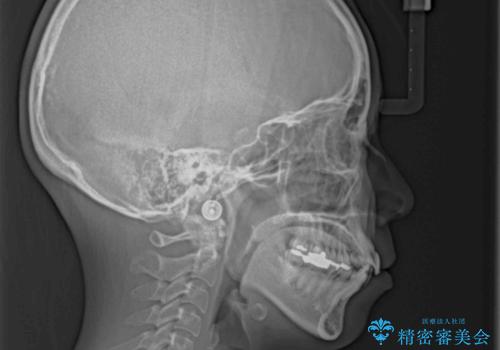

デコボコと口元の突出感 ハーフリンガルでの抜歯矯正

- 前歯のデコボコと上顎の前突感による口の閉じにくさを気にして来院された患者様です。

目立たない装置を希望されたので、上顎が裏側装置のハーフリンガルを選択し、上下左右の小臼歯(計4歯)を抜歯して矯正治療を行うこととしました。